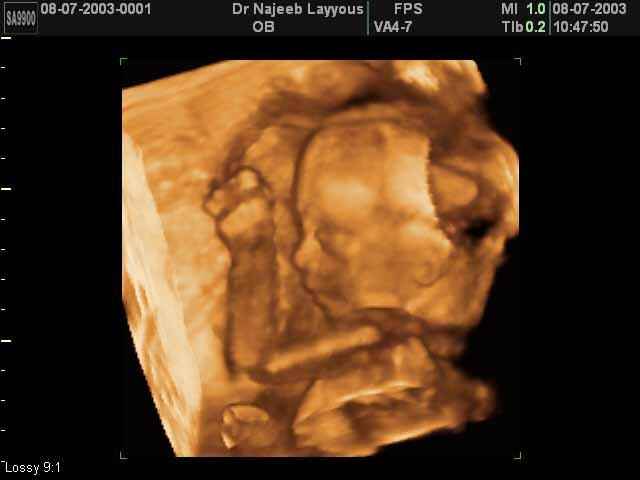

- 3D Fetal Profile Ultrasound Scan Photos

3D Fetal Profile Ultrasound Scan Photos | Dr N Layyous